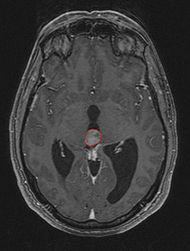

• Нейровизуализация. КТ, МРТ головного мозга визуализуют новообразование пинеальной локализации, выявляют окклюзию опухолью сильвиева водопровода, гидроцефалию. Пинеоцитома отличается чёткими контурами, при контрастировании - интенсивным гомогенным накоплением контрастного вещества. Отсутствие возможности проведения томографических исследований является показанием к эхоэнцефалографии, позволяющей определить объёмное образование по смещению серединного эхо-сигнала.